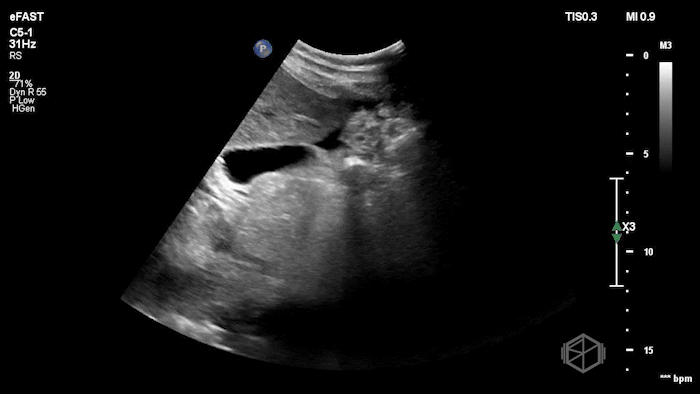

Drs. Ariz and Scavelli were caring for an approximately 40-year-old woman, G2P1, at approximately 8 weeks gestation, who presented to the ED with abdominal cramping. She was hypotensive on arrival, prompting the team to reach for the ultrasound immediately. They saw the following:

POCUS showed free fluid throughout the abdomen, including the RUQ, LUQ, and pelvis. The uterus was empty, and the final clip appears to show a complex left adnexal mass.

Diagnosis: Left ectopic pregnancy with hemoperitoneum